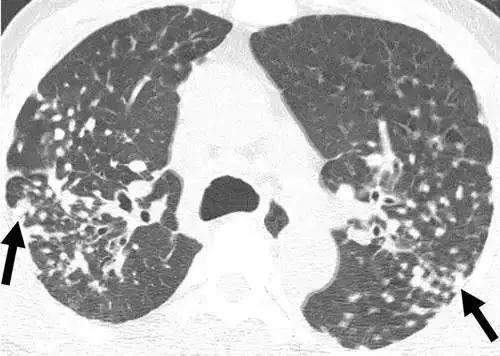

由于未注意防护,长期吸入无机粉尘,而在肺内形成了多发的小结节,同类的无机尘肺病多见于煤矿工、焊工、陶工以及石棉、云母、滑石、水泥等处理工人。

吸入有机粉尘同样也可引发肺结节的形成,例如采棉工人的棉尘肺、吸入谷物粉尘的农民肺以及暴露于木尘的木工等。下图是一位采棉女工,长期吸入植物性粉尘,在肺里形成很多微结节和索条状影。